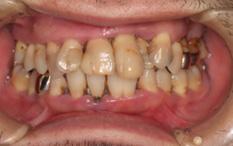

治療前 歯石、歯垢がたくさん付着していました。

![]() |